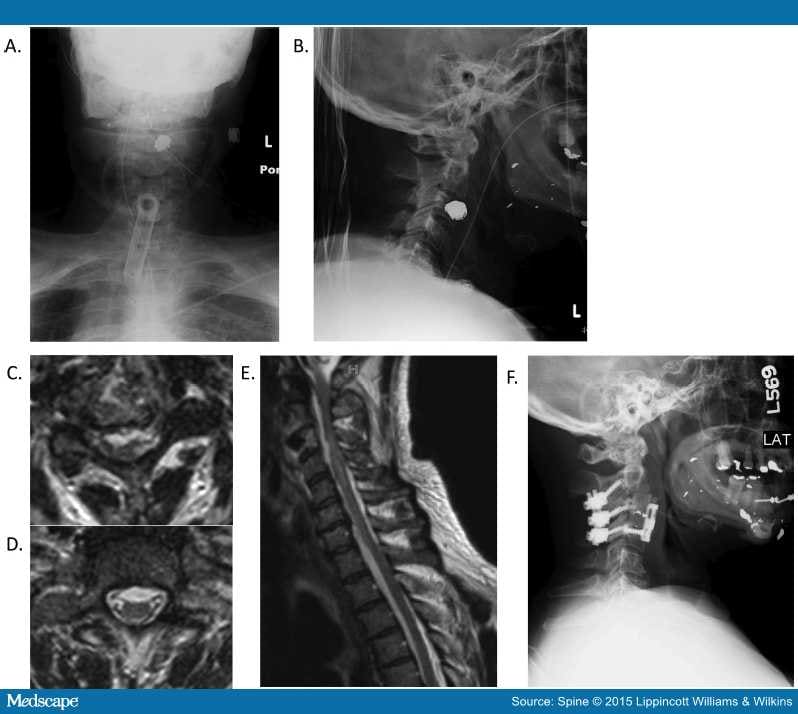

When Is Surgery Indicated for Patients with Gunshot Wounds to the Spine …

An Update on Civilian Spinal Gunshot Wounds

An Update on Civilian Spinal Gunshot Wounds